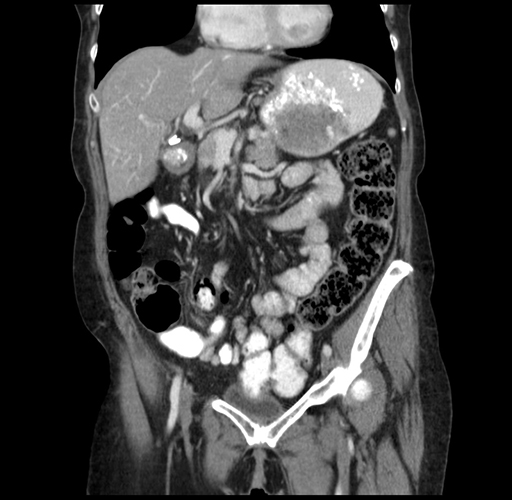

Pre-Chemo: Coronal Venous

Coronal Venous